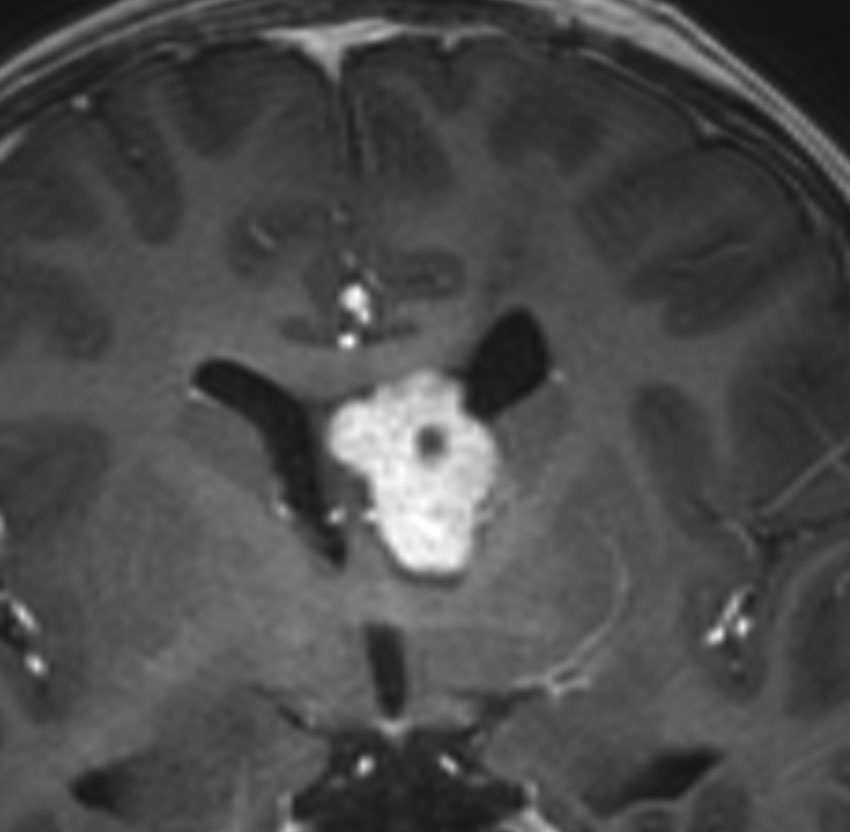

10歳の時に水頭症による頭痛と嘔吐で発症しました。結節性硬化症に合併したSEGAです。生検術,内視鏡手術,開頭術を受けて腫瘍を小さくして,その後にエベロリムスの投与を受けていました。これはエベロリムス投与後の画像です。この腫瘍にさらにエベロリムスの投与を続けるかという疑問があります。やめれば再燃することが多いからです。

結論として,これは完全摘出できるので摘出した方がいいです。なぜならそれでこの腫瘍は治癒するからです。右のFLAIR画像で見られるように発生部位となる尾状核のところでは一見,脳組織との境界が不明瞭にみえるのですが,腫瘍はある程度の硬さがあるので脳組織との区別をすることができて,完全摘出できるものです。